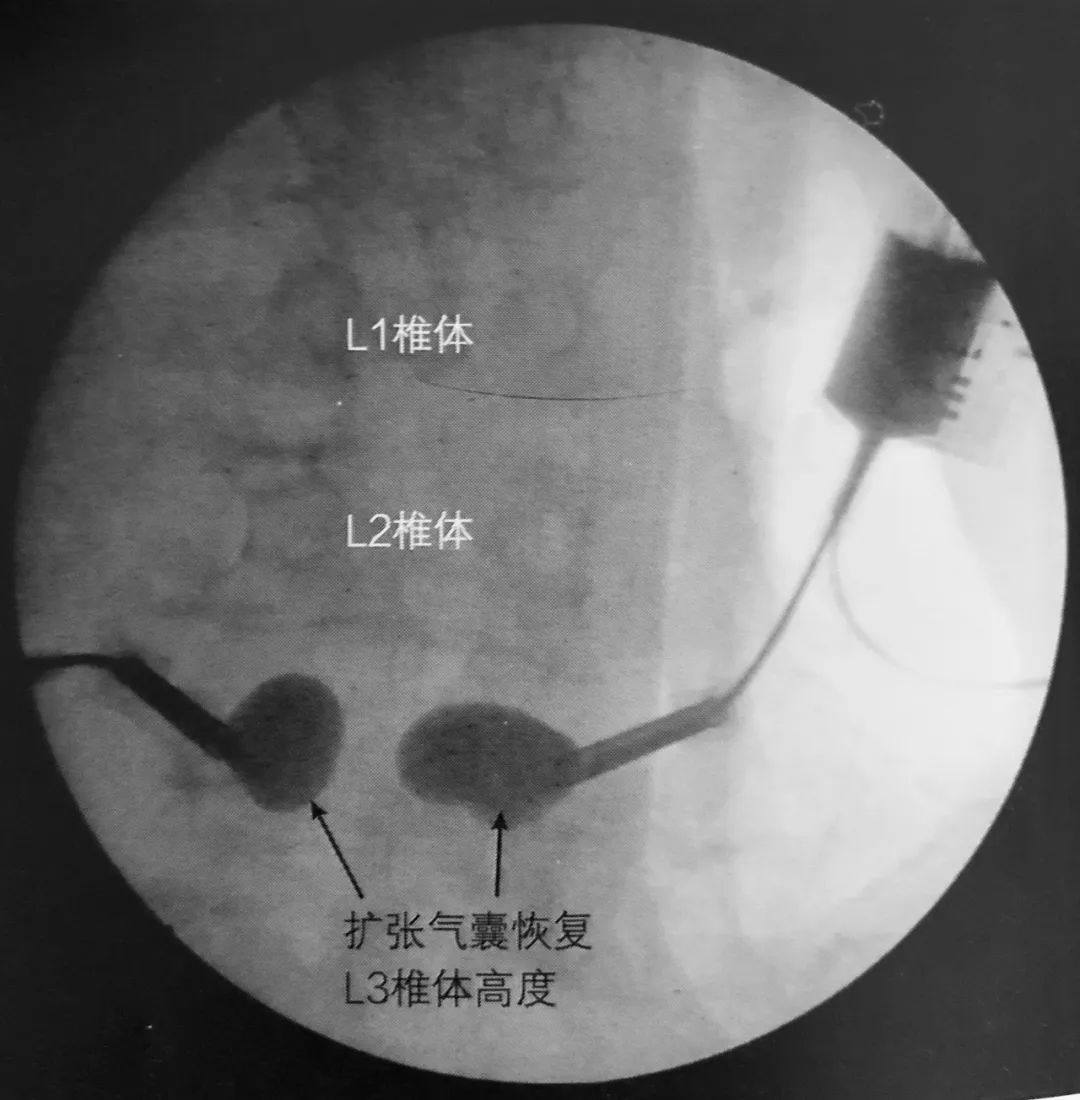

5. 术中透视证实球囊位于椎体前部,这可避免骨折块向后突入椎管。

6. 球囊充气为骨水泥注入建立潜在空间。

7. 透视下向椎体内注入骨水泥,在正侧位片上仔细观察以确保椎体边缘不被侵犯。如果发现骨水泥溢出,则停止注入。应避免将骨水泥注入椎体后部。